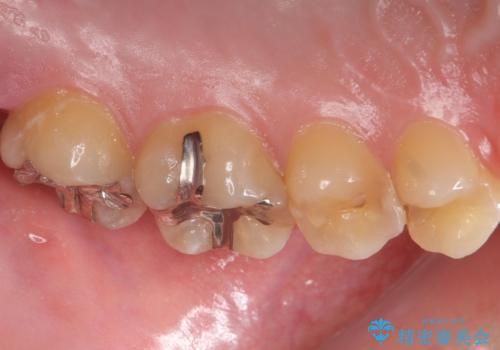

- 奥歯が欠けてしみるとのことで来院された患者様です。

かなり大きな虫歯であることと、清掃不良により歯全体が脱灰していたため、クラウンでの修復処置を行います。

奥に生えている親知らずも清掃不良であったため、今回治療する歯の清掃性を高めるために抜歯を行います。